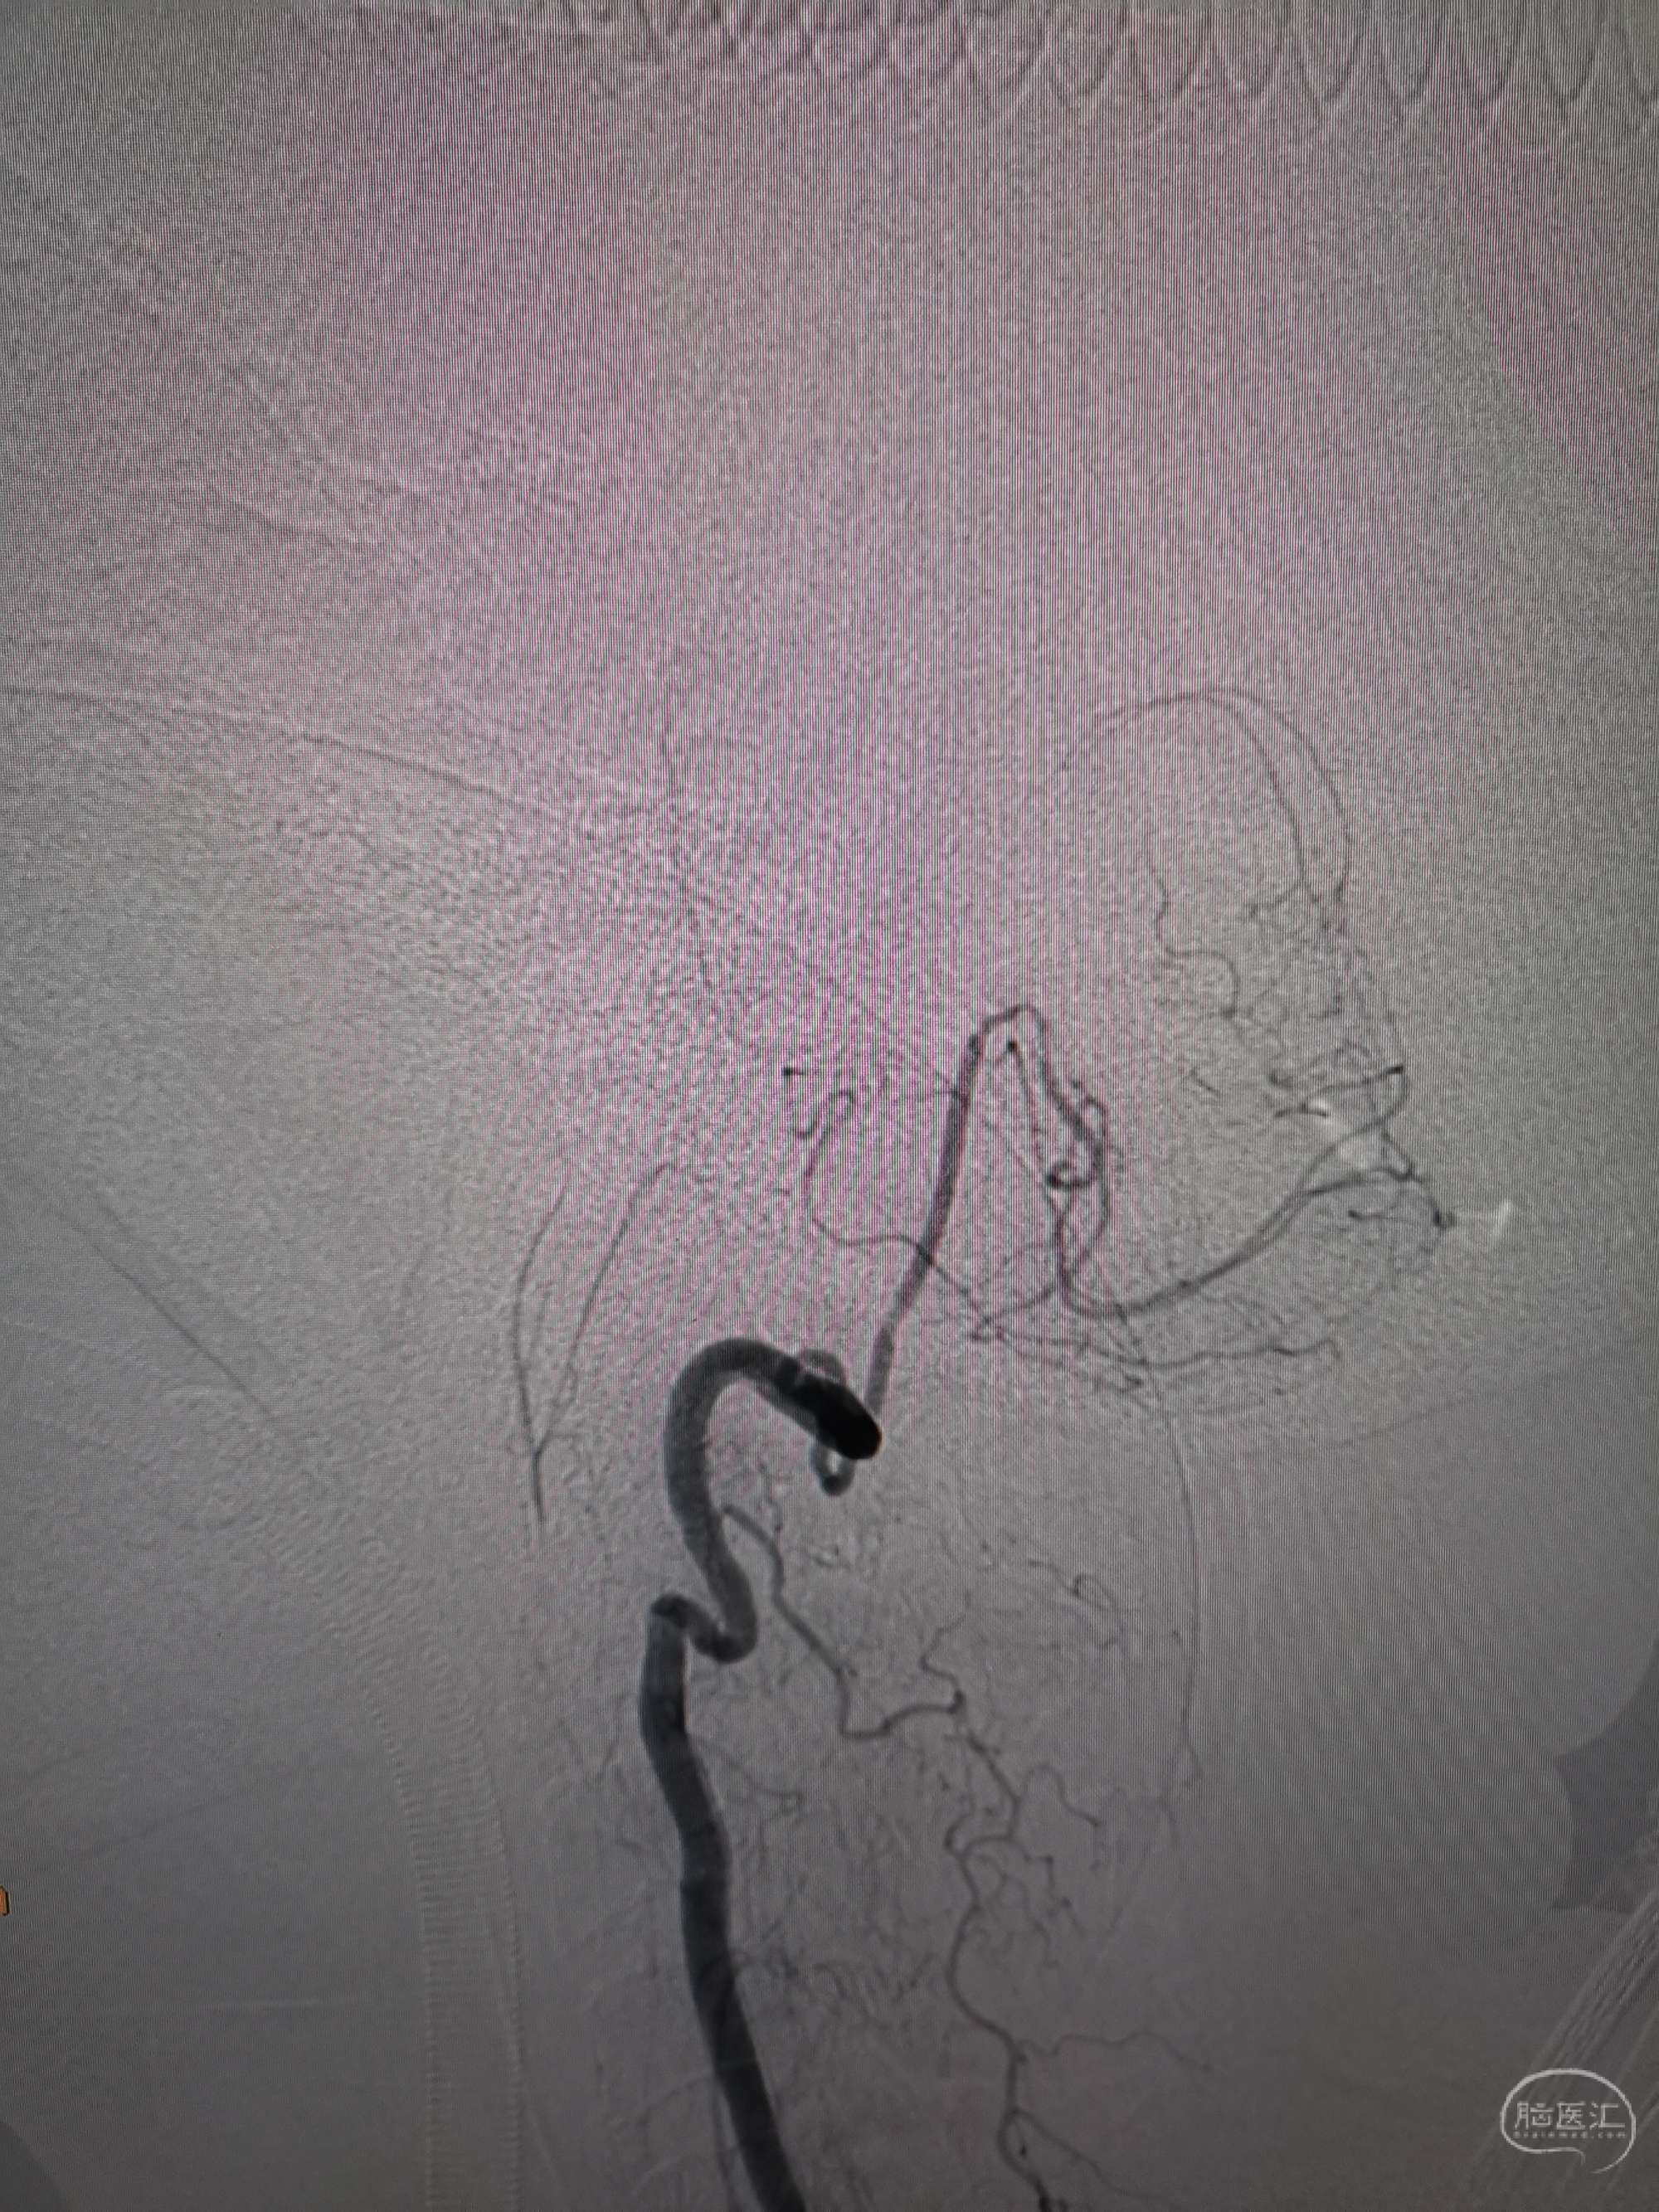

术前再次造影评估

右侧椎动脉穿支供血及左侧PICA供血较入院时略有改善,但改善不明显。故按计划行左侧椎动脉再通术